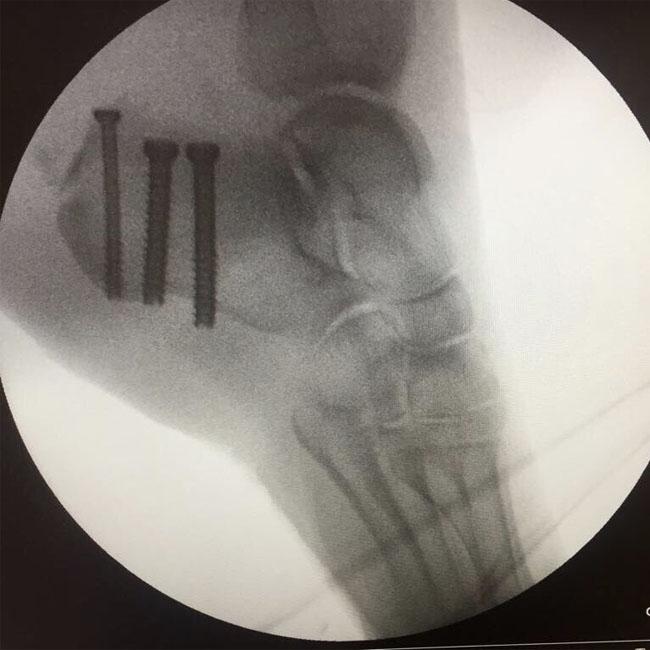

Gary, 46, took to his Twitter account to share an X-ray of Dawn’s foot with his 4.48 million followers on the social media site.

The X-ray shows that Dawn has had to have three screws in the heel bone of her foot to fix the break.

The ‘Rule The World’ singer captioned the snap: "Poor Dawn #happyxmas #bestfootforward (sic)".